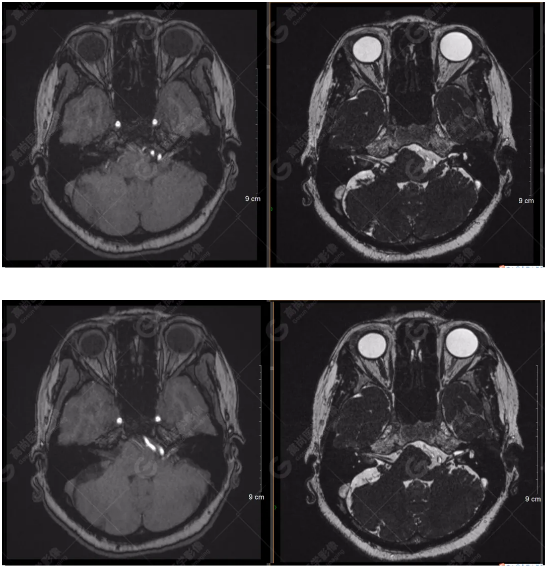

顱腦MRA及ciss序列示腦基底動脈環(huán)完整,雙側(cè)頸內(nèi)動脈末段、大腦前動脈、大腦中動脈、大腦后動脈及其主要分支顯影良好,管徑及走行正常,無明顯局灶性增粗或變細(xì)。雙側(cè)椎動脈末段沿延髓左側(cè)向上走行,左側(cè)面聽神經(jīng)輕度受壓移位,左側(cè)面聽神經(jīng)周圍見細(xì)小血管包繞。右側(cè)面聽神經(jīng)及雙側(cè)三叉神經(jīng)周圍未見異常血管影。

1.雙側(cè)椎動脈末段沿延髓左側(cè)向上走行,左側(cè)面聽神經(jīng)輕度受壓移位,左側(cè)面聽神經(jīng)周圍見細(xì)小血管包繞,可符合面聽神經(jīng)壓迫綜合征。

2.右側(cè)顳部蛛網(wǎng)膜囊腫。